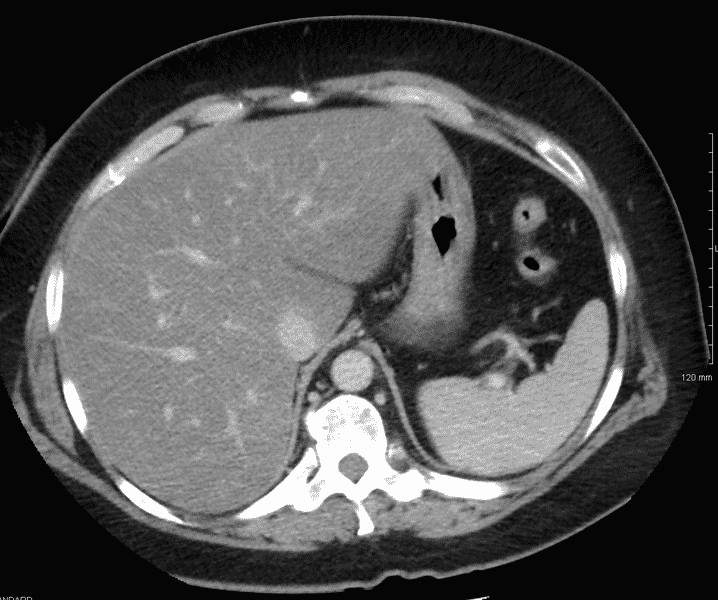

- УЗИ (определяют изменения структуры, выявляют кисты).

- КТ (определяют изменения структуры, определяют степень поражения).

- МРТ (оценка степени увеличения печени и изменений в ткани печени).